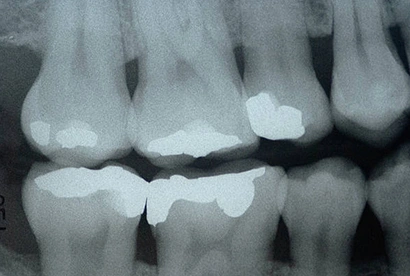

Digital Bitewings

Digital bitewings help us capture detailed images of the upper and lower teeth in a specific area of the mouth. They are particularly useful for detecting decay between teeth, assessing bone health for signs of gum disease, and evaluating the fit of dental crowns. Although some patients may have unpleasant memories of traditional intraoral bitewings, we prioritize patient comfort and use the latest technology to make the process as comfortable as possible.